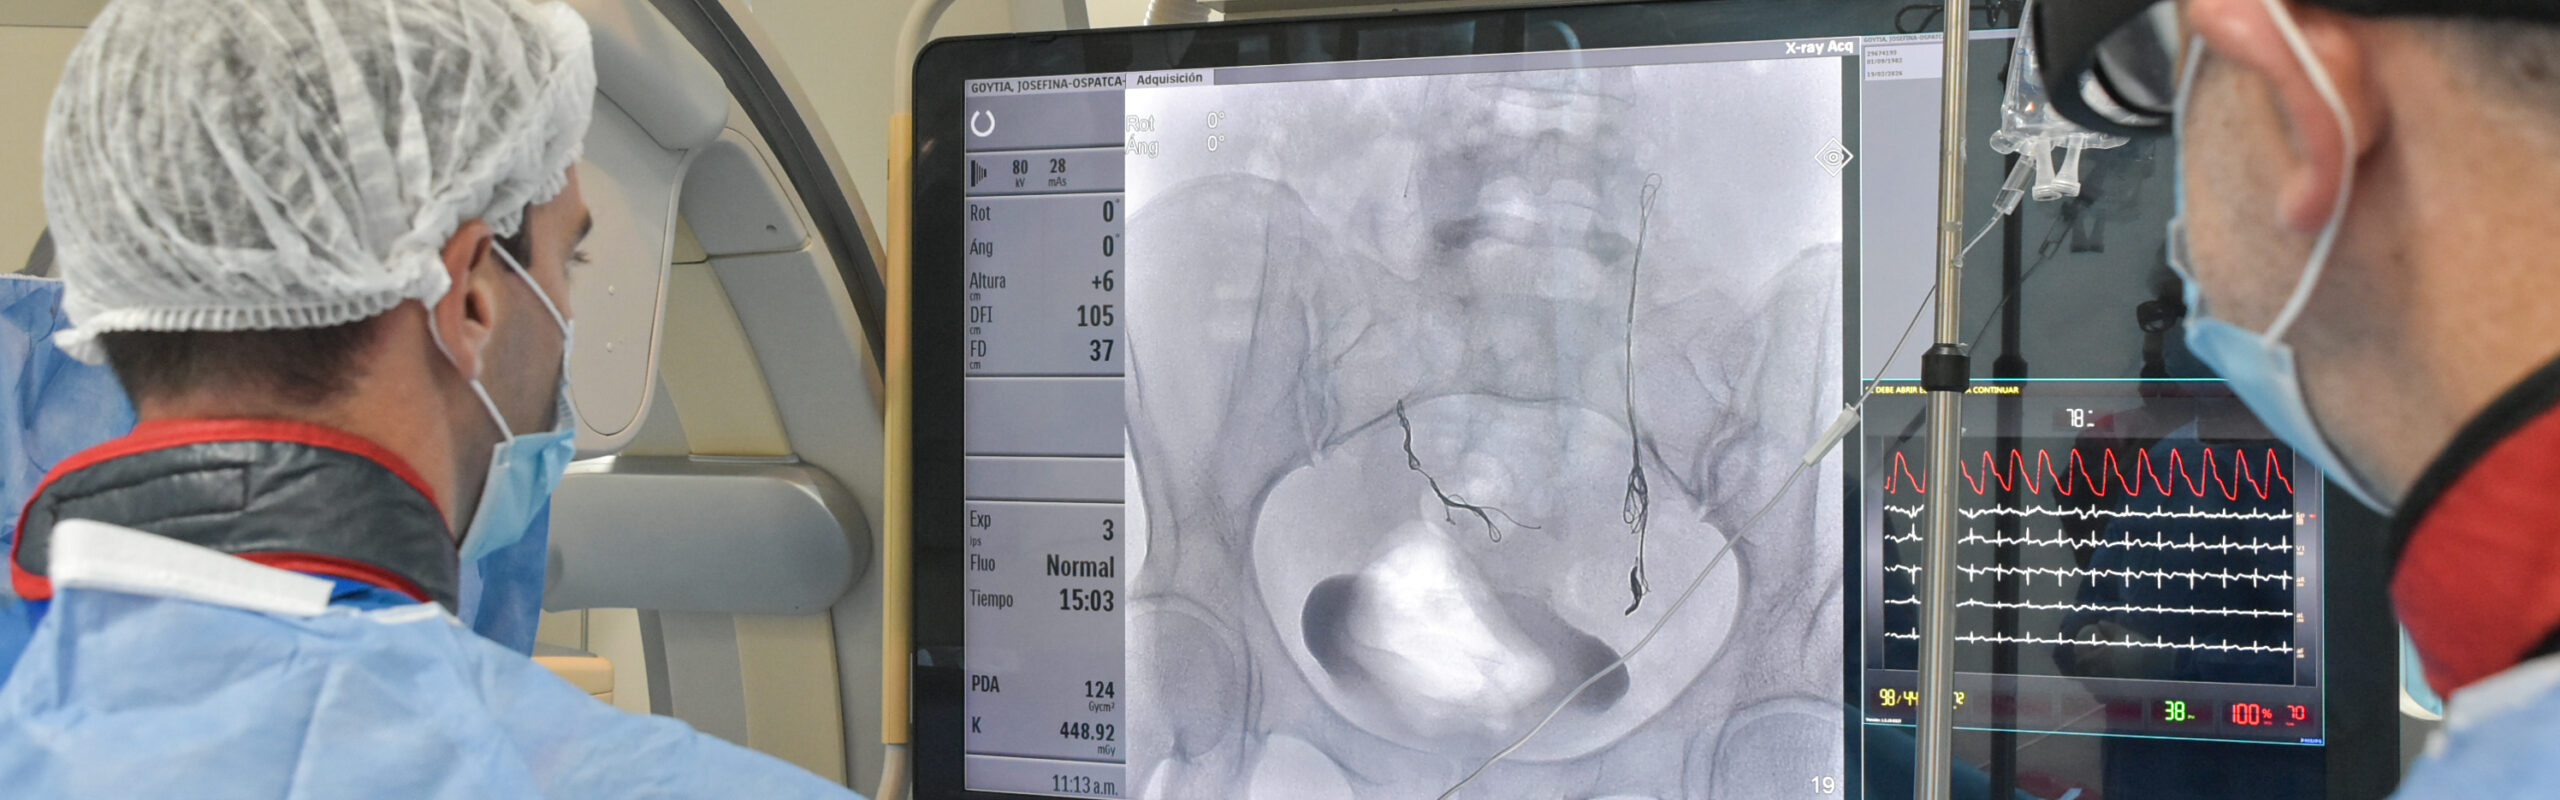

EMBOLIZACIÓN ÚTERO-OVÁRICA EN HEMODINAMIA

Monte Grande, 8 de abril de 2026 – El procedimiento, de carácter endovascular y mínimamente invasivo, permitió tratar el síndrome de congestión pélvica mediante la oclusión de las venas gonadales, dando respuesta a una patología que genera dolor crónico y otras afecciones.